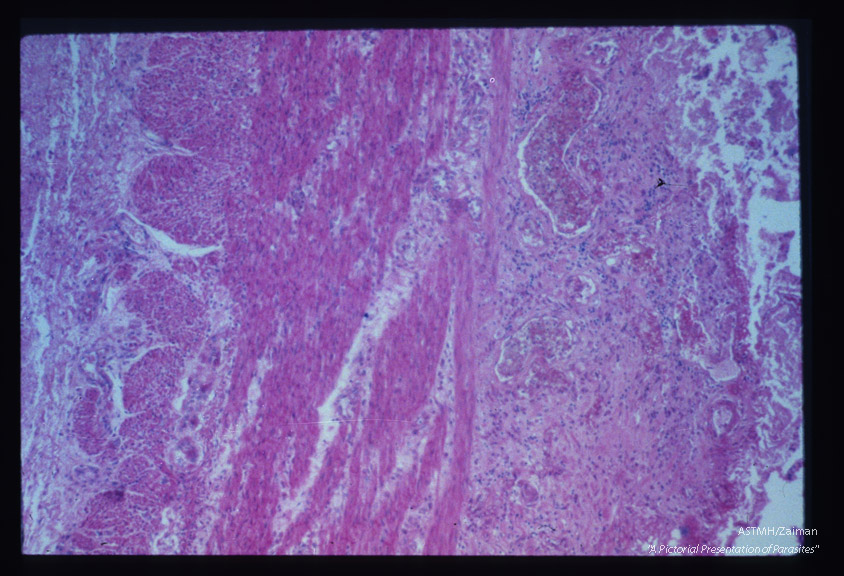

Chronic inflammatory response in region of bowel ulcer.

Entamoeba histolytica

Description: Chronic inflammatory response in region of bowel ulcer.